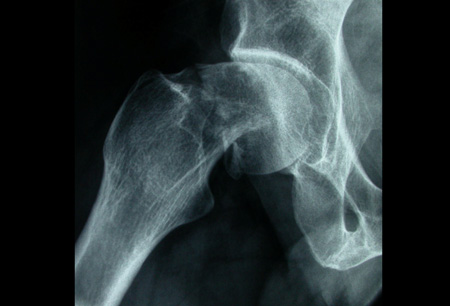

Con los tipos de fractura extracapsulares, la estabilidad de las fracturas desplazadas generalmente tiene en cuenta el grado de conminución y, más específicamente, la conminución de la corteza medial. Los tipos de fracturas intertrocantéricas simples de 2 fragmentos sin conminución del calcar medial (corteza) generalmente se consideran estables. Las fracturas intertrocantéricas de 3 y 4 fragmentos con ruptura de la corteza posteromedial o la fractura con oblicuidad invertida se consideran inestables.[3][51][Figure caption and citation for the preceding image starts]: Radiografía anteroposterior inicial que muestra una fractura intracapsular de la cadera izquierda desplazadaDe la colección de Bradley A. Petrisor, MSc, MD, FRCSC y de Mohit Bhandari, MD, MSc, FRCSC [Citation ends].